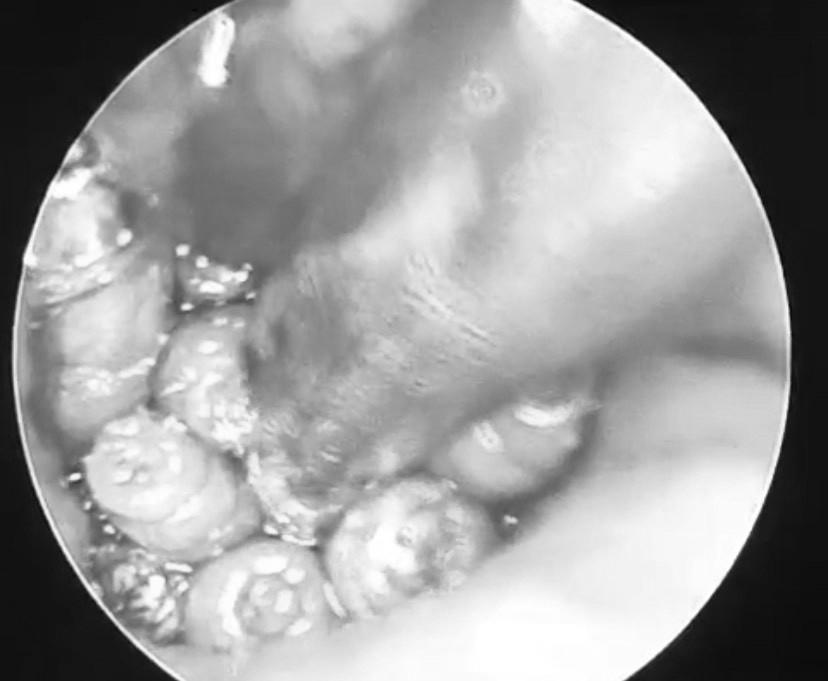

Các bác sĩ tiến hành nội soi và phát hiện ống tai hẹp, đọng nhiều máu tươi. Khi hút sạch máu, ê-kíp quan sát thấy dị vật màu trắng di động, nhiều hình ảnh giống con giòi lấp đầy hòm nhĩ, màng nhĩ thủng rộng. Bệnh nhân được tiến hành nội soi, gắp hàng chục con giòi sống trong tai giữa.

Theo bác sĩ CKII Đinh Viết Thanh, Trưởng khoa Tai Mũi Họng, đây là trường hợp rất hiếm gặp ở bệnh nhân có tiền sử bị viêm tai giữa, có mủ sẽ thu hút ruồi cái đến đẻ trứng và phát triển thành giòi sau vài giờ.